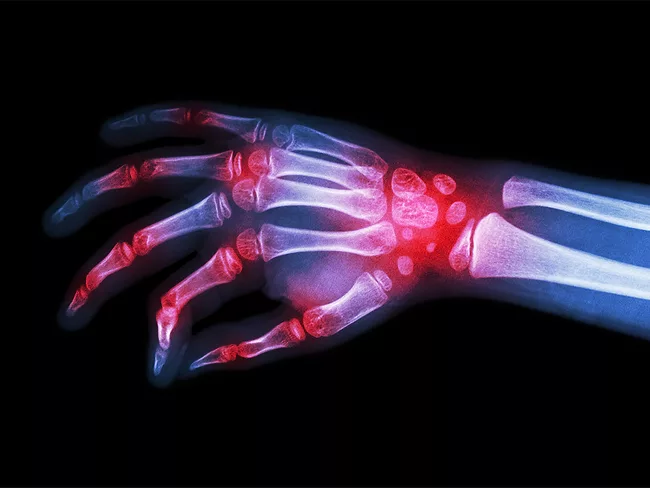

X-ray image of hand and wrist

T cells store lipids and die in rheumatoid arthritis joints

In the inflamed joints of rheumatoid arthritis, CD4+ T lymphocytes accumulate lipid droplets that make them vulnerable and promote their death, thereby amplifying joint inflammation. A study led by scientists at Mayo Clinic and Stanford University suggests that blocking the formation of these lipid droplets or their contents could offer a therapeutic strategy for this condition.